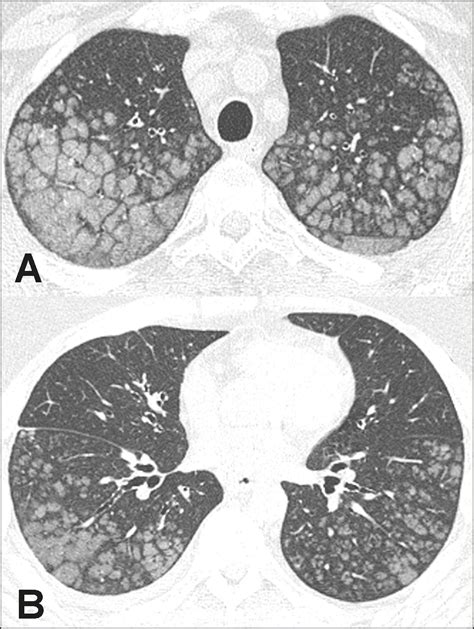

• Chest X-ray: A chest X-ray can reveal the presence of calcium deposits in the lungs.

• CT Scan: A computed tomography (CT) scan provides detailed images of the lungs and can help identify the location and extent of the calcification.

Calcification in lungs refers to the abnormal deposition of calcium salts in the lung tissue. This process can affect the lungs' structure and function, leading to various respiratory issues. The calcium deposits can form in different parts of the lung, including the alveoli, bronchi, and blood vessels. The severity and impact of calcification in lungs can vary widely depending on the underlying cause and the extent of the deposits.